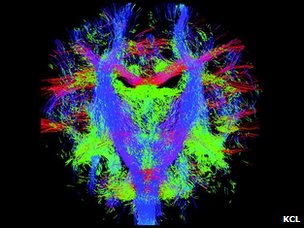

这张动态的脑神经路径图可以被用来按图索骥,解读不同的脑神经之间如何沟通、交流和联结的。

伦敦大学国王学院、帝国理工大学和牛津大学附属医院的儿科专家们的制图目标是希望能精确地、动态地图解脑神经信息传递线路和流程,在最细微具体的层次显示脑神经系统的发育成型过程。

新生儿的脑神经纤维束

这张动态图的意义最直接的体现,或许是在胎儿出生前三个月内,如果发现脑神经系统有异常,医生能够及早确诊并干预。

这项研究的核心是MRI扫描技术的更新,使得科学家得以精确捕捉以前力所难及的胎儿脑神经系统成长的细节。

不过,也有科学家认为,扫描得到的图像与脑神经系统线路的实际状况可能有相当的差距,即使绘制出这样一张动态的路径图,能提供的或许只是宏观指引。